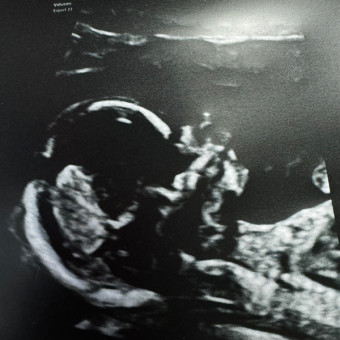

We’re so excited to welcome baby Butler in February 2026 surrounded by the love and support of our friends and family!! Thank you for spoiling our sweet baby BOY! 🧸🩵 Diaper Raffle will take place at shower. All sizes welcome!